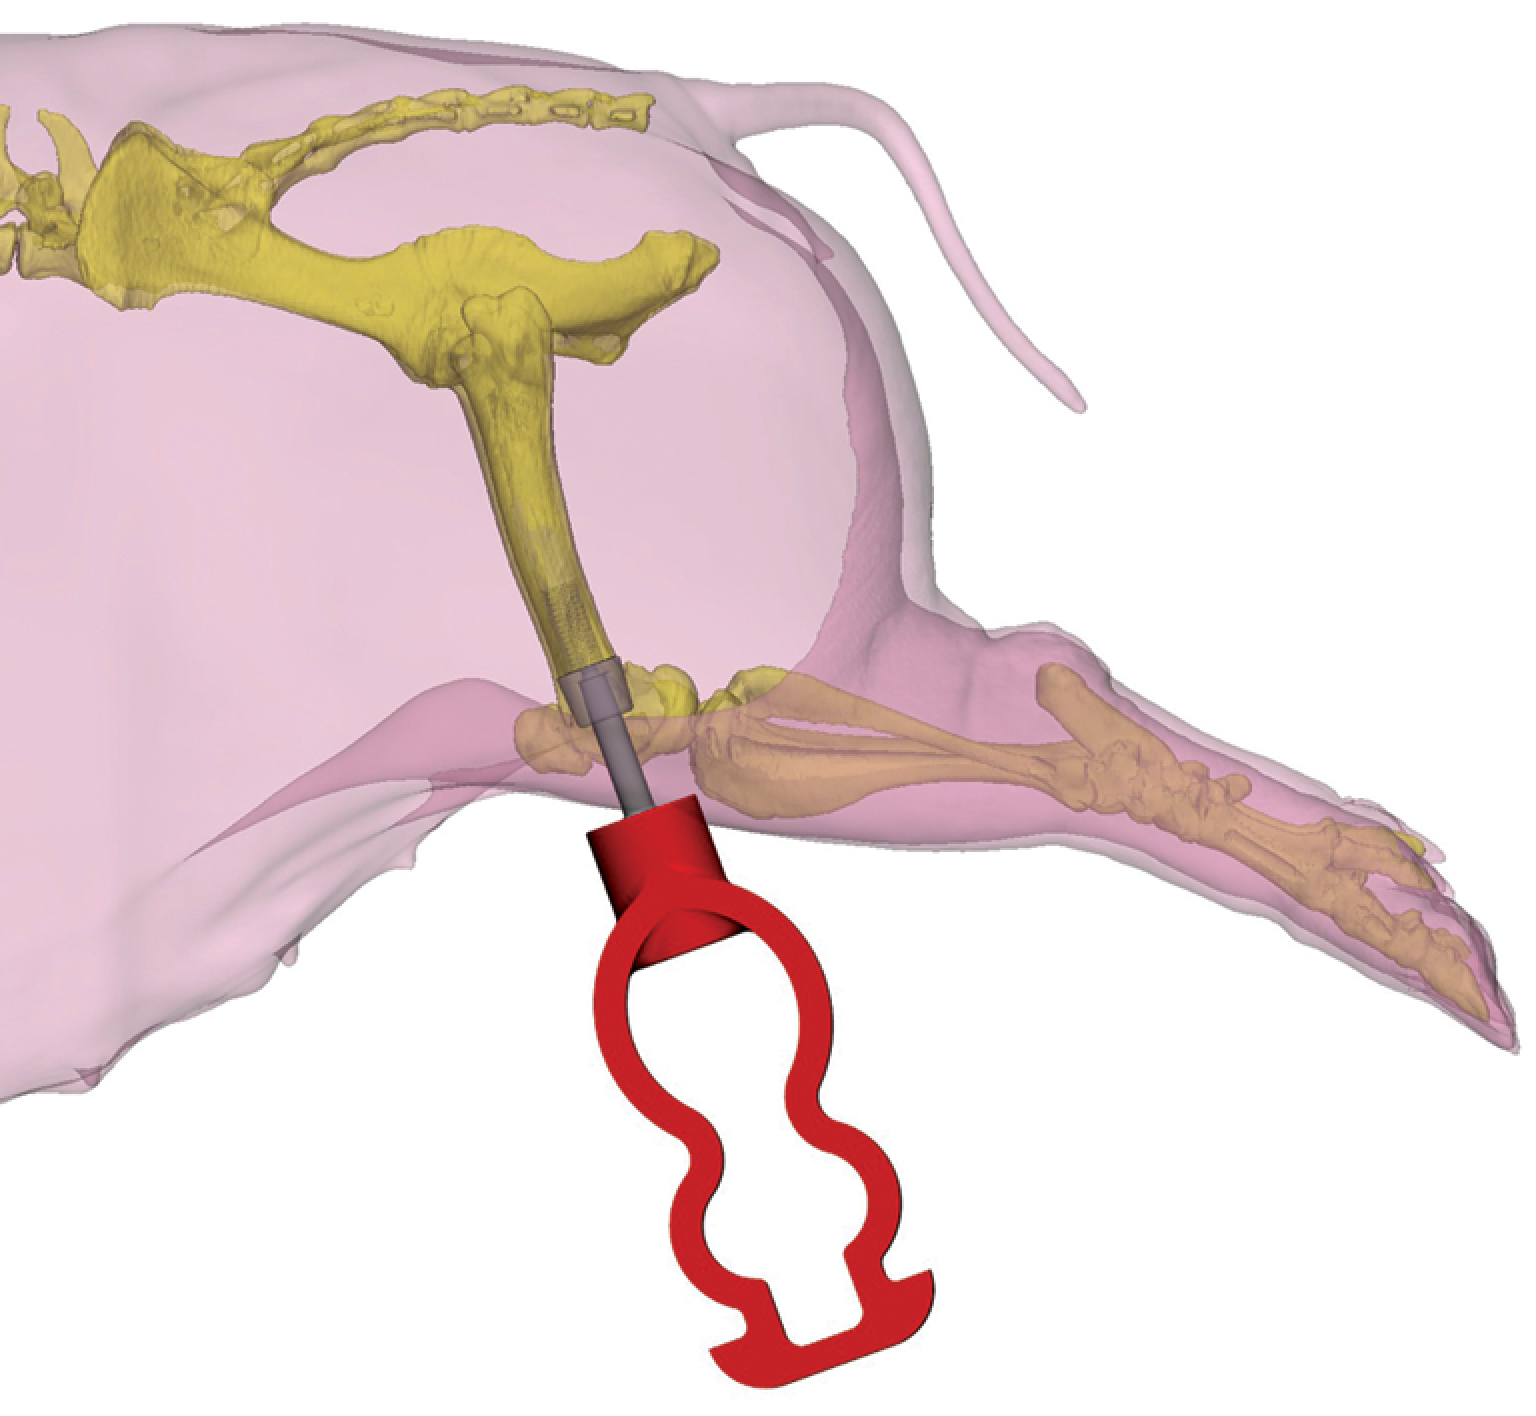

С целью индивидуализации размеров интрамедуллярной части имплантата животному под седацией была выполнена компьютерная томография (КТ). На основании КТ были определены и скорректированы диаметр и длина интрамедуллярного компонента имплантата для соответствия анатомическим параметрам костномозгового канала бедренной кости животного (рис. 1). Предоперационное планирование включало трехмерную реконструкцию и виртуальное моделирование позиционирования имплантата (рис. 2).

Рисунок 2. 3D-модель имплантата и экзопротеза, установленных в заднюю конечность животного